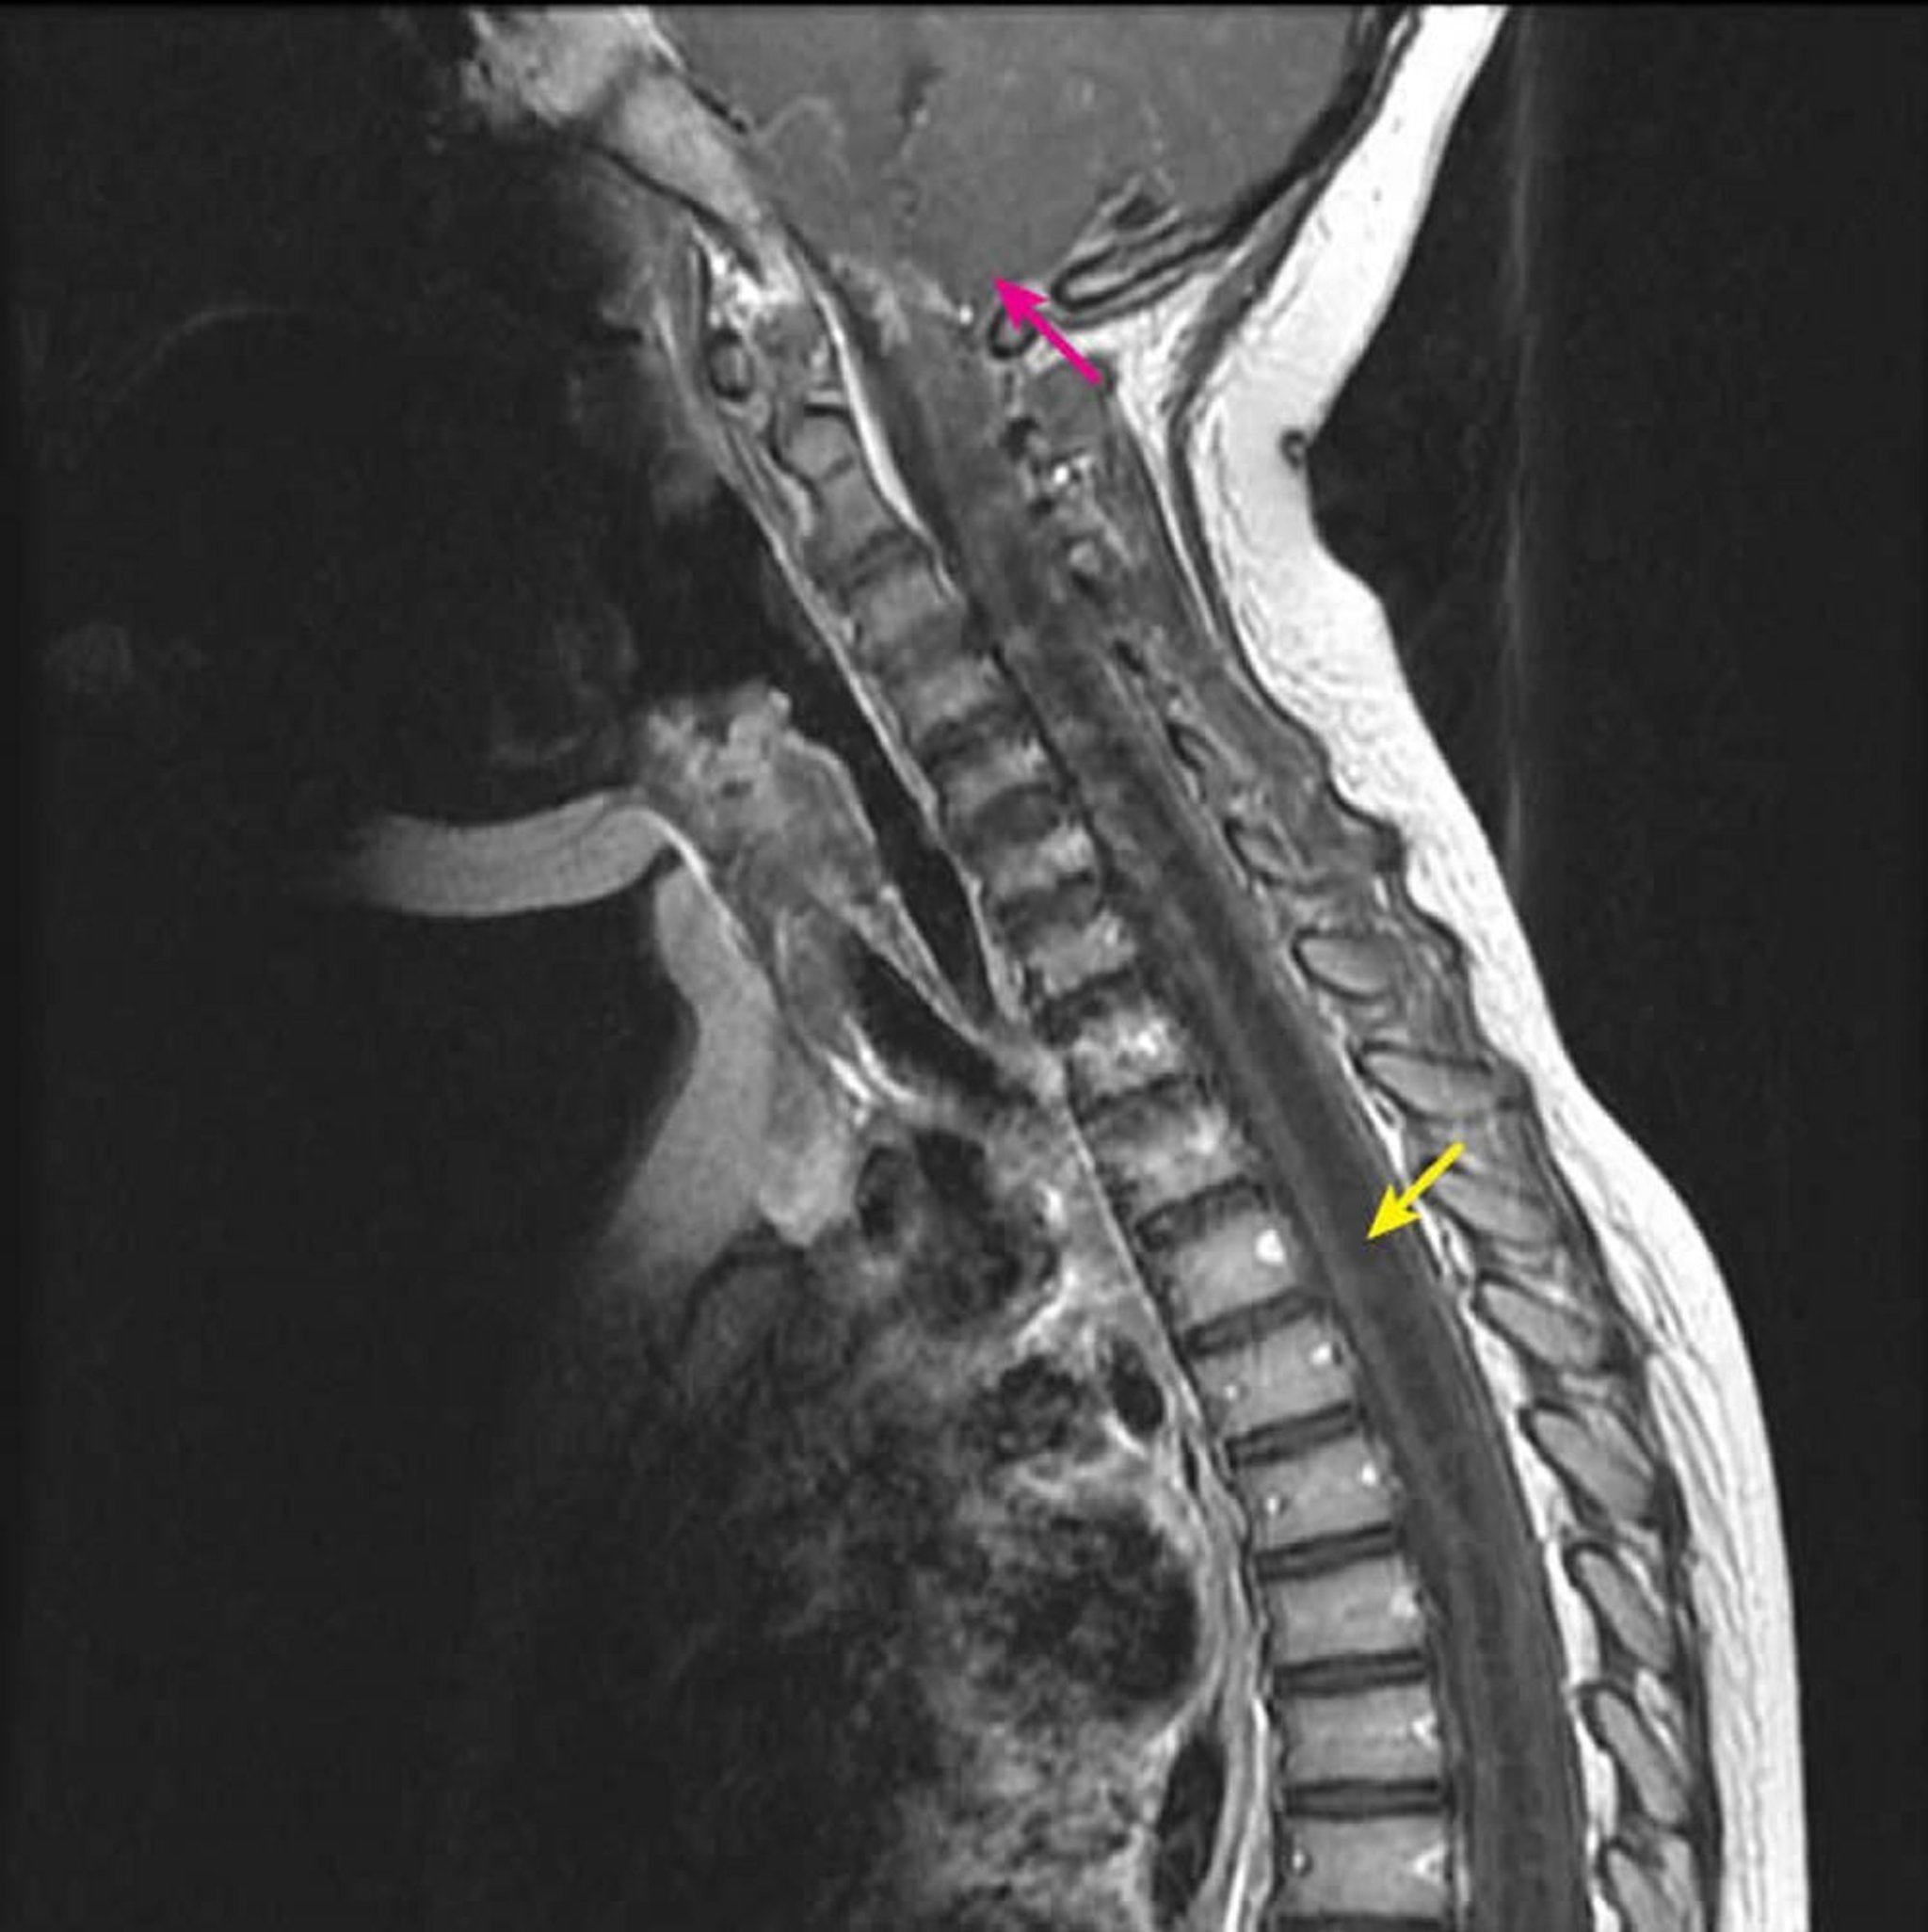

Сагиттальная постконтрастная T1-взвешенная МРТ показывает большую гипоинтенсивную интрамедуллярную полость в спинном мозге T1, характерную для свища (желтая стрелка). У ребенка с установленной мальформацией Киари 1 типа (розовая стрелка) она простирается вниз от уровня шейных позвонков C2-C3. Это явление определяется как сирингогидромиелия, потому что сирингомиелия (эксцентрическая полость в спинном мозге) не может быть дифференцирована от гидромиелии (полость в центральном канале спинного мозга) посредством визуализации.

Courtesy of John Tsiouris, MD, Division of Neuroradiology, New York–Presbyterian Hospital/Weill Cornell Medical Center.